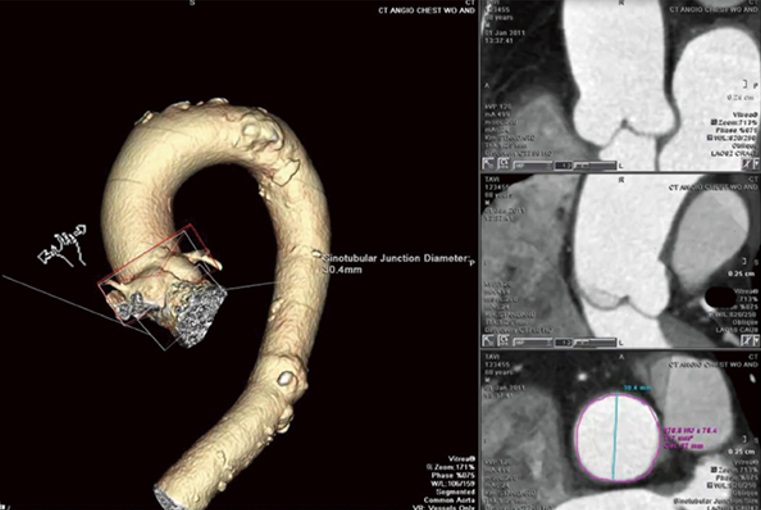

Приклад CAAS S-Valve software